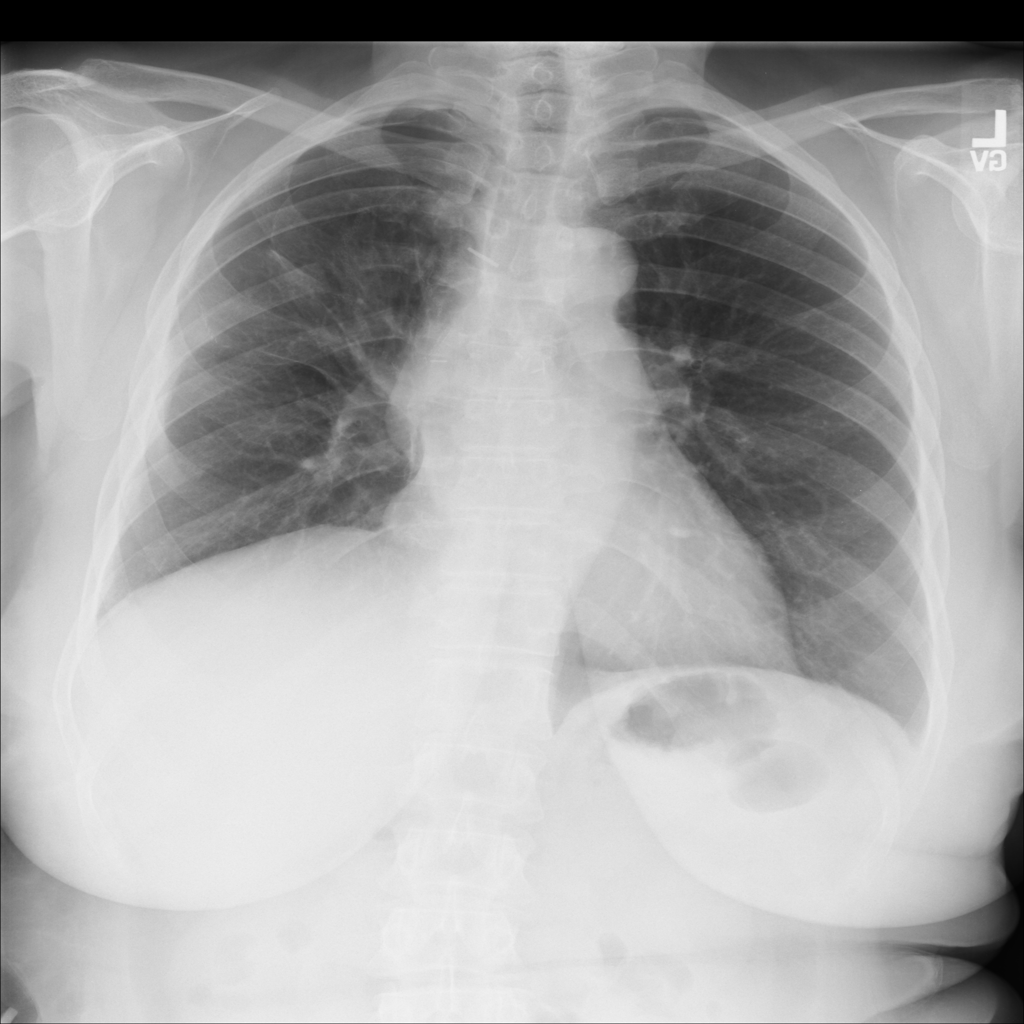

Pneumothorax

Pneumothorax means air is present outside the lung in the pleural space, which can allow part of the lung to collapse. It is an important imaging finding because the size and clinical impact can vary widely.

Showing up to 90 reference images for Pneumothorax.

PAT-4639 · IMG-011Pneumothorax

PAT-4639 · IMG-011

AP